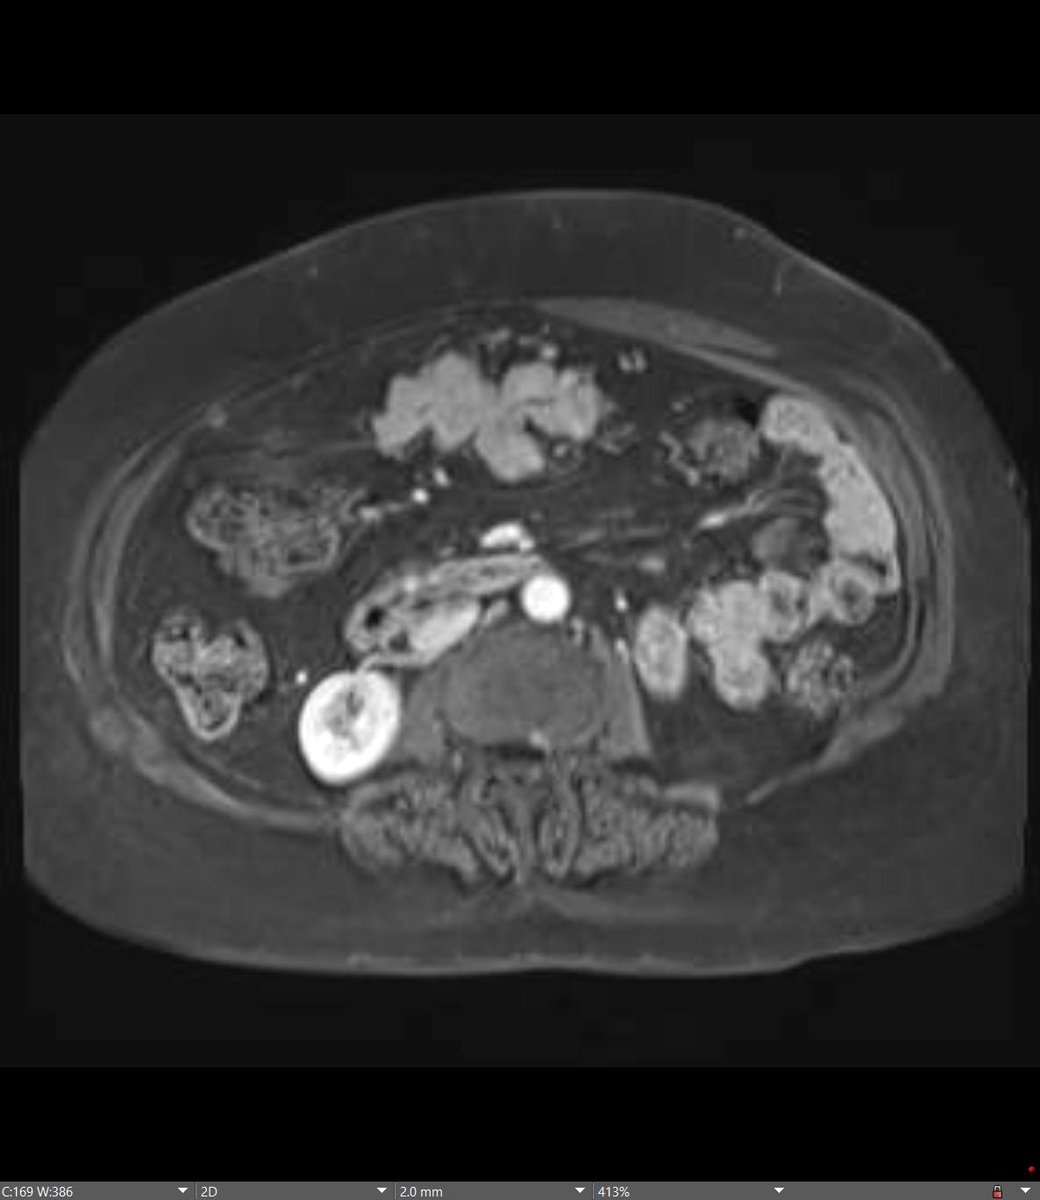

60-year-old male patient with history of cirrhosis undergoes HCC screening with non contrast MRI (patient refuses IV gadolinium due to hives)... Diagnosis? Next step? @BrighamRad @FOAMrad @SAR_RFS @futureradres @ARRS_Radiology @Abdominal_Rad @CBRadiologia #MedEd

All right, all right... Where is the spleen? This patient is status post splenectomy for trauma. MRI performed 5 years later confirming benign vs indolent etiology... this is... Mesenteric SPLENOSIS! @BrighamRad @FOAMrad @SAR_RFS @futureradres @ARRS_Radiology @Abdominal_Rad